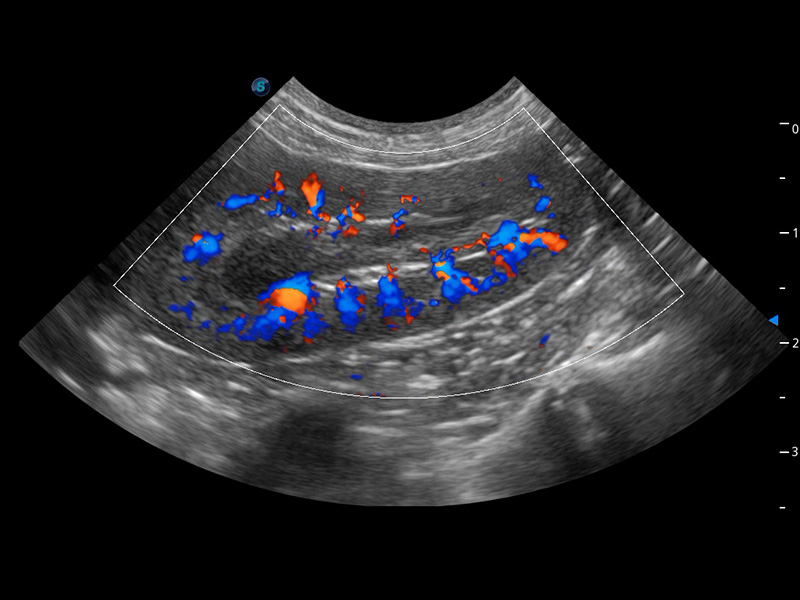

ProPet 60 作为一款高端台式动物超声设备,为动物医生的日常诊断提供了一系列贴合动物临床需求、解决临床实际问题的高级成像功能。凭借全系列高清探头,满足医生对腹部、心脏、生殖、浅表、肌骨等成像的所有需求,切实帮助您提升检查效率,提高诊断信心。